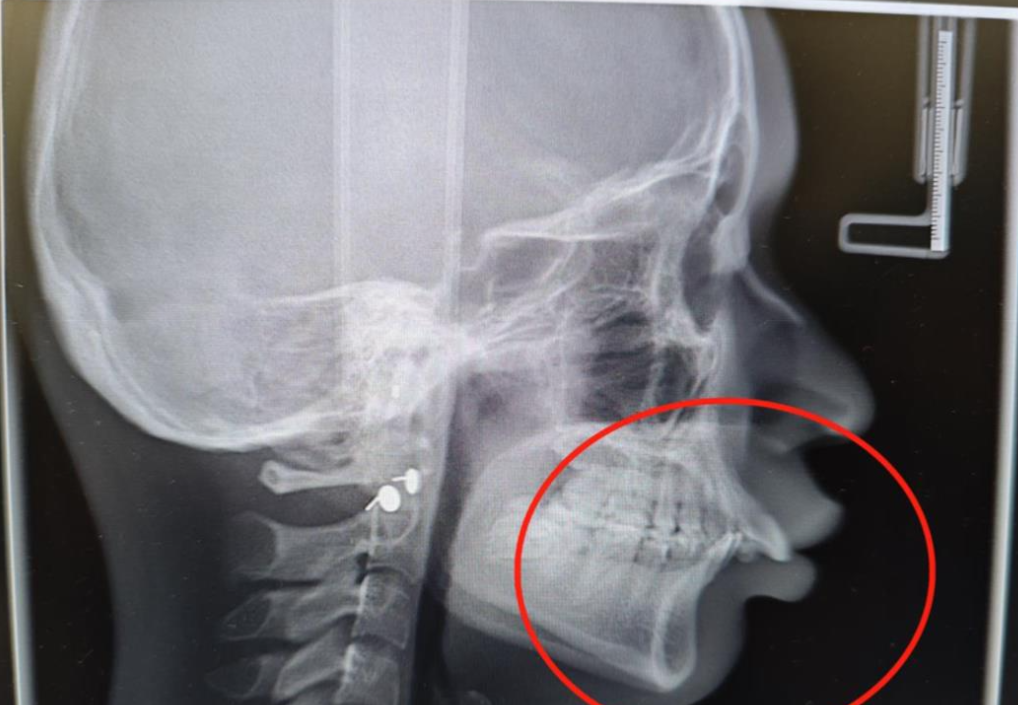

近 3 年时间里,医生根据牙齿移动的情况,平均每 7~10 天 3D 打印一套牙套,到现在已有 60 多副。最新拍片可见,小宁有了明显变化,上颌骨、牙齿成功回缩。